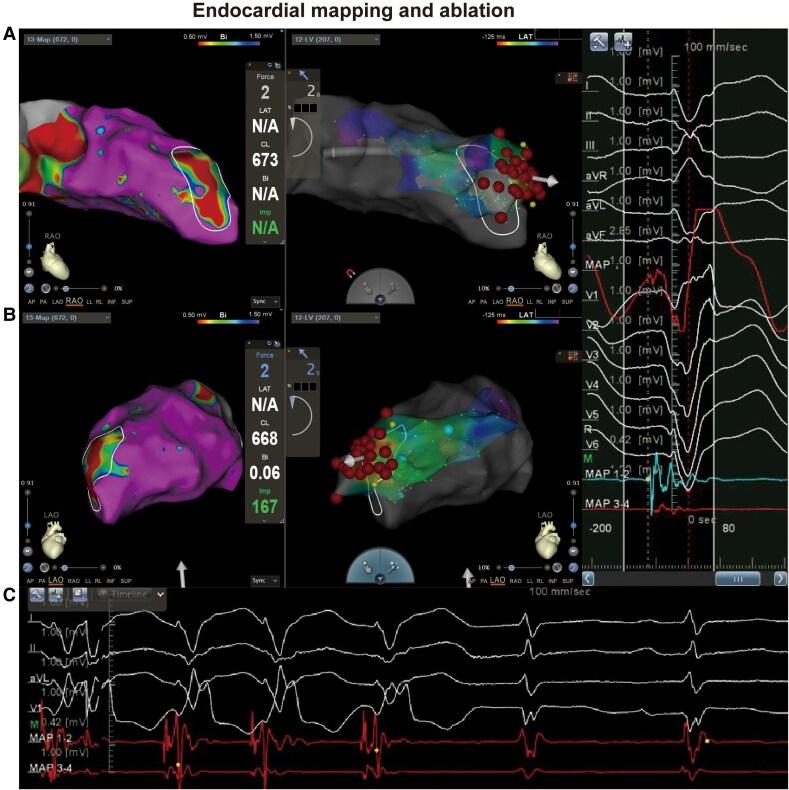

心肌梗死后难治性室性心律失常的室性心动过速模拟辅助消融病例报告:放电前定位。

Case report of ventricular tachycardia simulation facilitated ablation for refractory ventricular arrhythmia post-myocardial infarction: aiming before firing.

CASE SUMMARY

The present describes a case of refractory VA after unsuccessful endocardial ablation associated with a previous myocardial infarction. Consequently, the successful attempts were implemented through transcoronary venous ethanol ablation targeted at the site of epicardial sustained re-entry in the simulation process, generated from cardiac late gadolinium-enhanced magnetic resonance imaging.

心肌梗死后室性心律失常(VA)的管理面临重大挑战,因为其发病率和死亡率很高,特别是在药物治疗无效的情况下。在某些情况下,致心律失常的解剖基质位于心外膜。因此,通过心内膜导管消融实现透壁损伤一直是不可行的。

病例摘要

本文描述了一例既往心肌梗死后心内膜消融失败后难治性VA的病例。因此,在心脏延迟钆增强磁共振成像模拟过程中,针对心外膜持续折返部位进行经冠状静脉乙醇消融,成功完成了治疗。